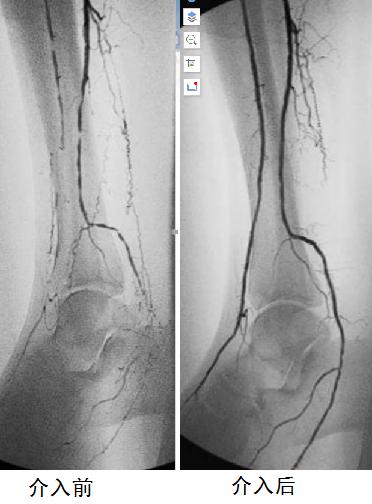

首先,通过介入血管插管,可以在远离病变、容易操作的部位简便实施。插入的细小导管可顺着血管走行,进行选择性血管造影,从而准确直观地显示出血管堵塞的部位、范围和程度,是诊断血管病变的“金标准”,为下一步的治疗提供有力的依据。

血管造影可清晰显示狭窄闭塞情况,腔内介入快捷有效